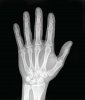

This mean I need some help please on turning about 20-30 of greyscale images such as:

To images which use colour in this style:

(as you can see, dense things - which would represent bone - are blue; medium things - representing the soft tissue - are orange; and thin/'soft' things - representing air or fluid - are green).